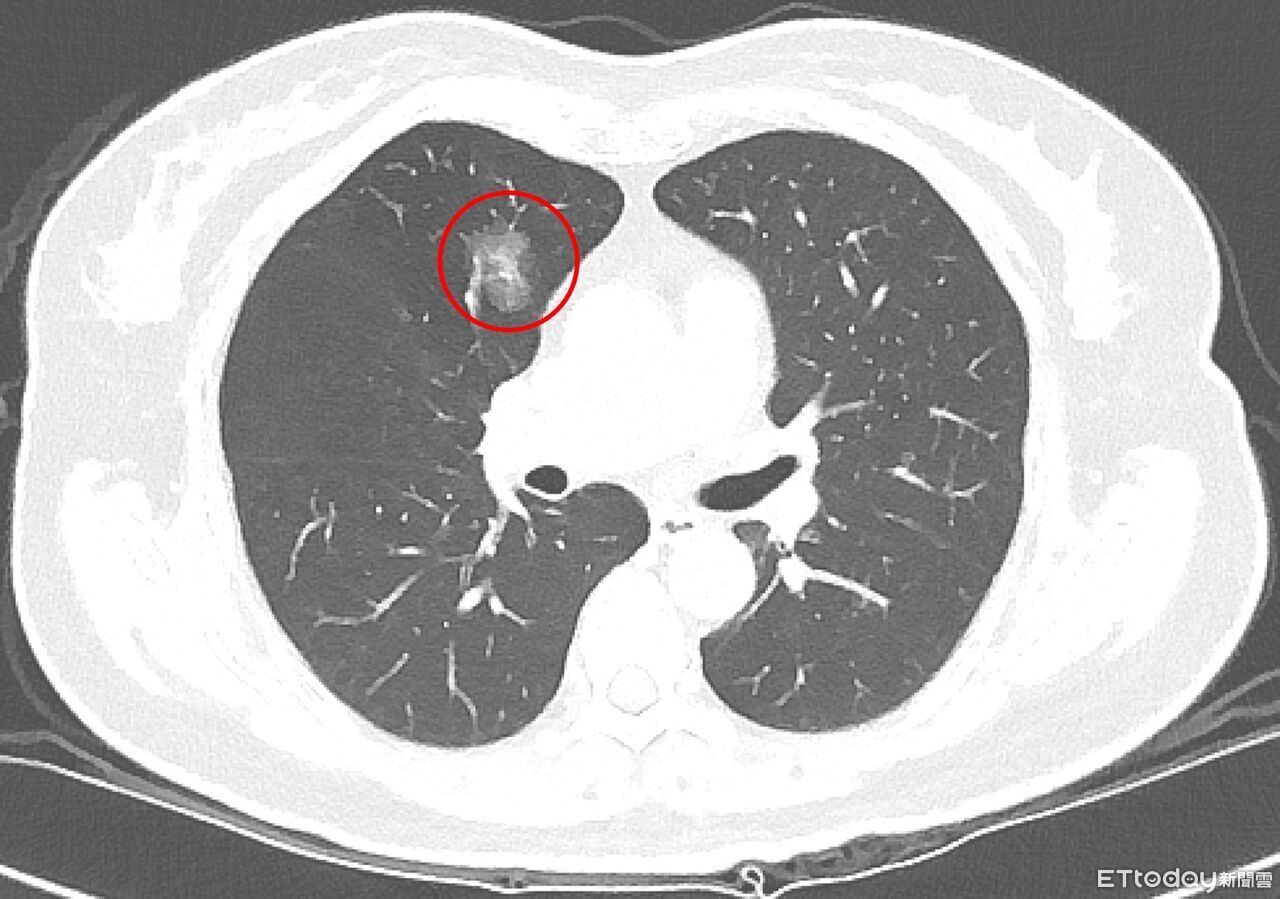

▲極早期的微小肺部結節。若醫師難以判讀,應定期追蹤。(圖/台北慈院提供)

吳智偉舉例,一名64歲女性無抽菸習慣、無家族史,健檢發現1.2公分肺結節,後來持續追蹤7年,增至1.4公分,最終決定手術,才確診為第1期肺腺癌;因屬早期發現,術後無需化療,恢復良好,也顯示長期追蹤有助掌握變化、及時處置。

吳智偉提醒,早期的結節因體積小,部分甚至無法進行切片,目前多以0.8公分作為基本判斷門檻;當影像一時難以判讀,更應規律追蹤,若後續擴大或特徵改變,再與醫師討論是否進一步治療。